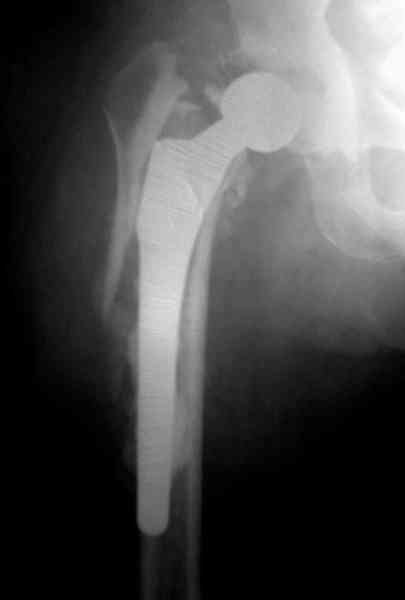

Приглашенный хирург установил ревизионный вариант бедренного компонента без замены ацетабулярного компонента, что осложнилось нагноением и свищами на уровне сустава и средней трети бедра. После двухгодичного безуспешного лечения перевязками и антибиотиками больная обратилась к нам на консультацию.

Повторная операция по удалению тотального протеза с irrigation&debridment, канал после очистки цемента обильно промыт и рассверлен римером.

Для спейсера в бедро использовал старый длинный бедренний компонент меньшего диаметра, облепленный со всех сторон цементом с антибиотиком.